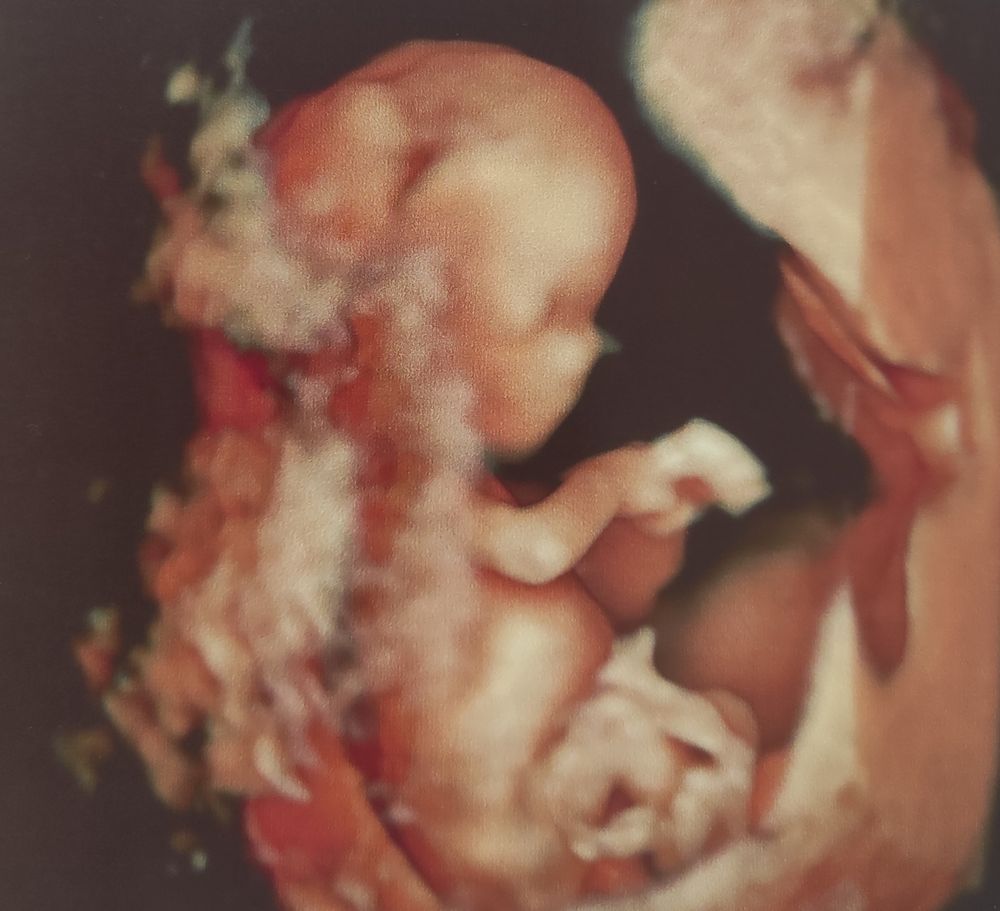

Ну, и фото на память)